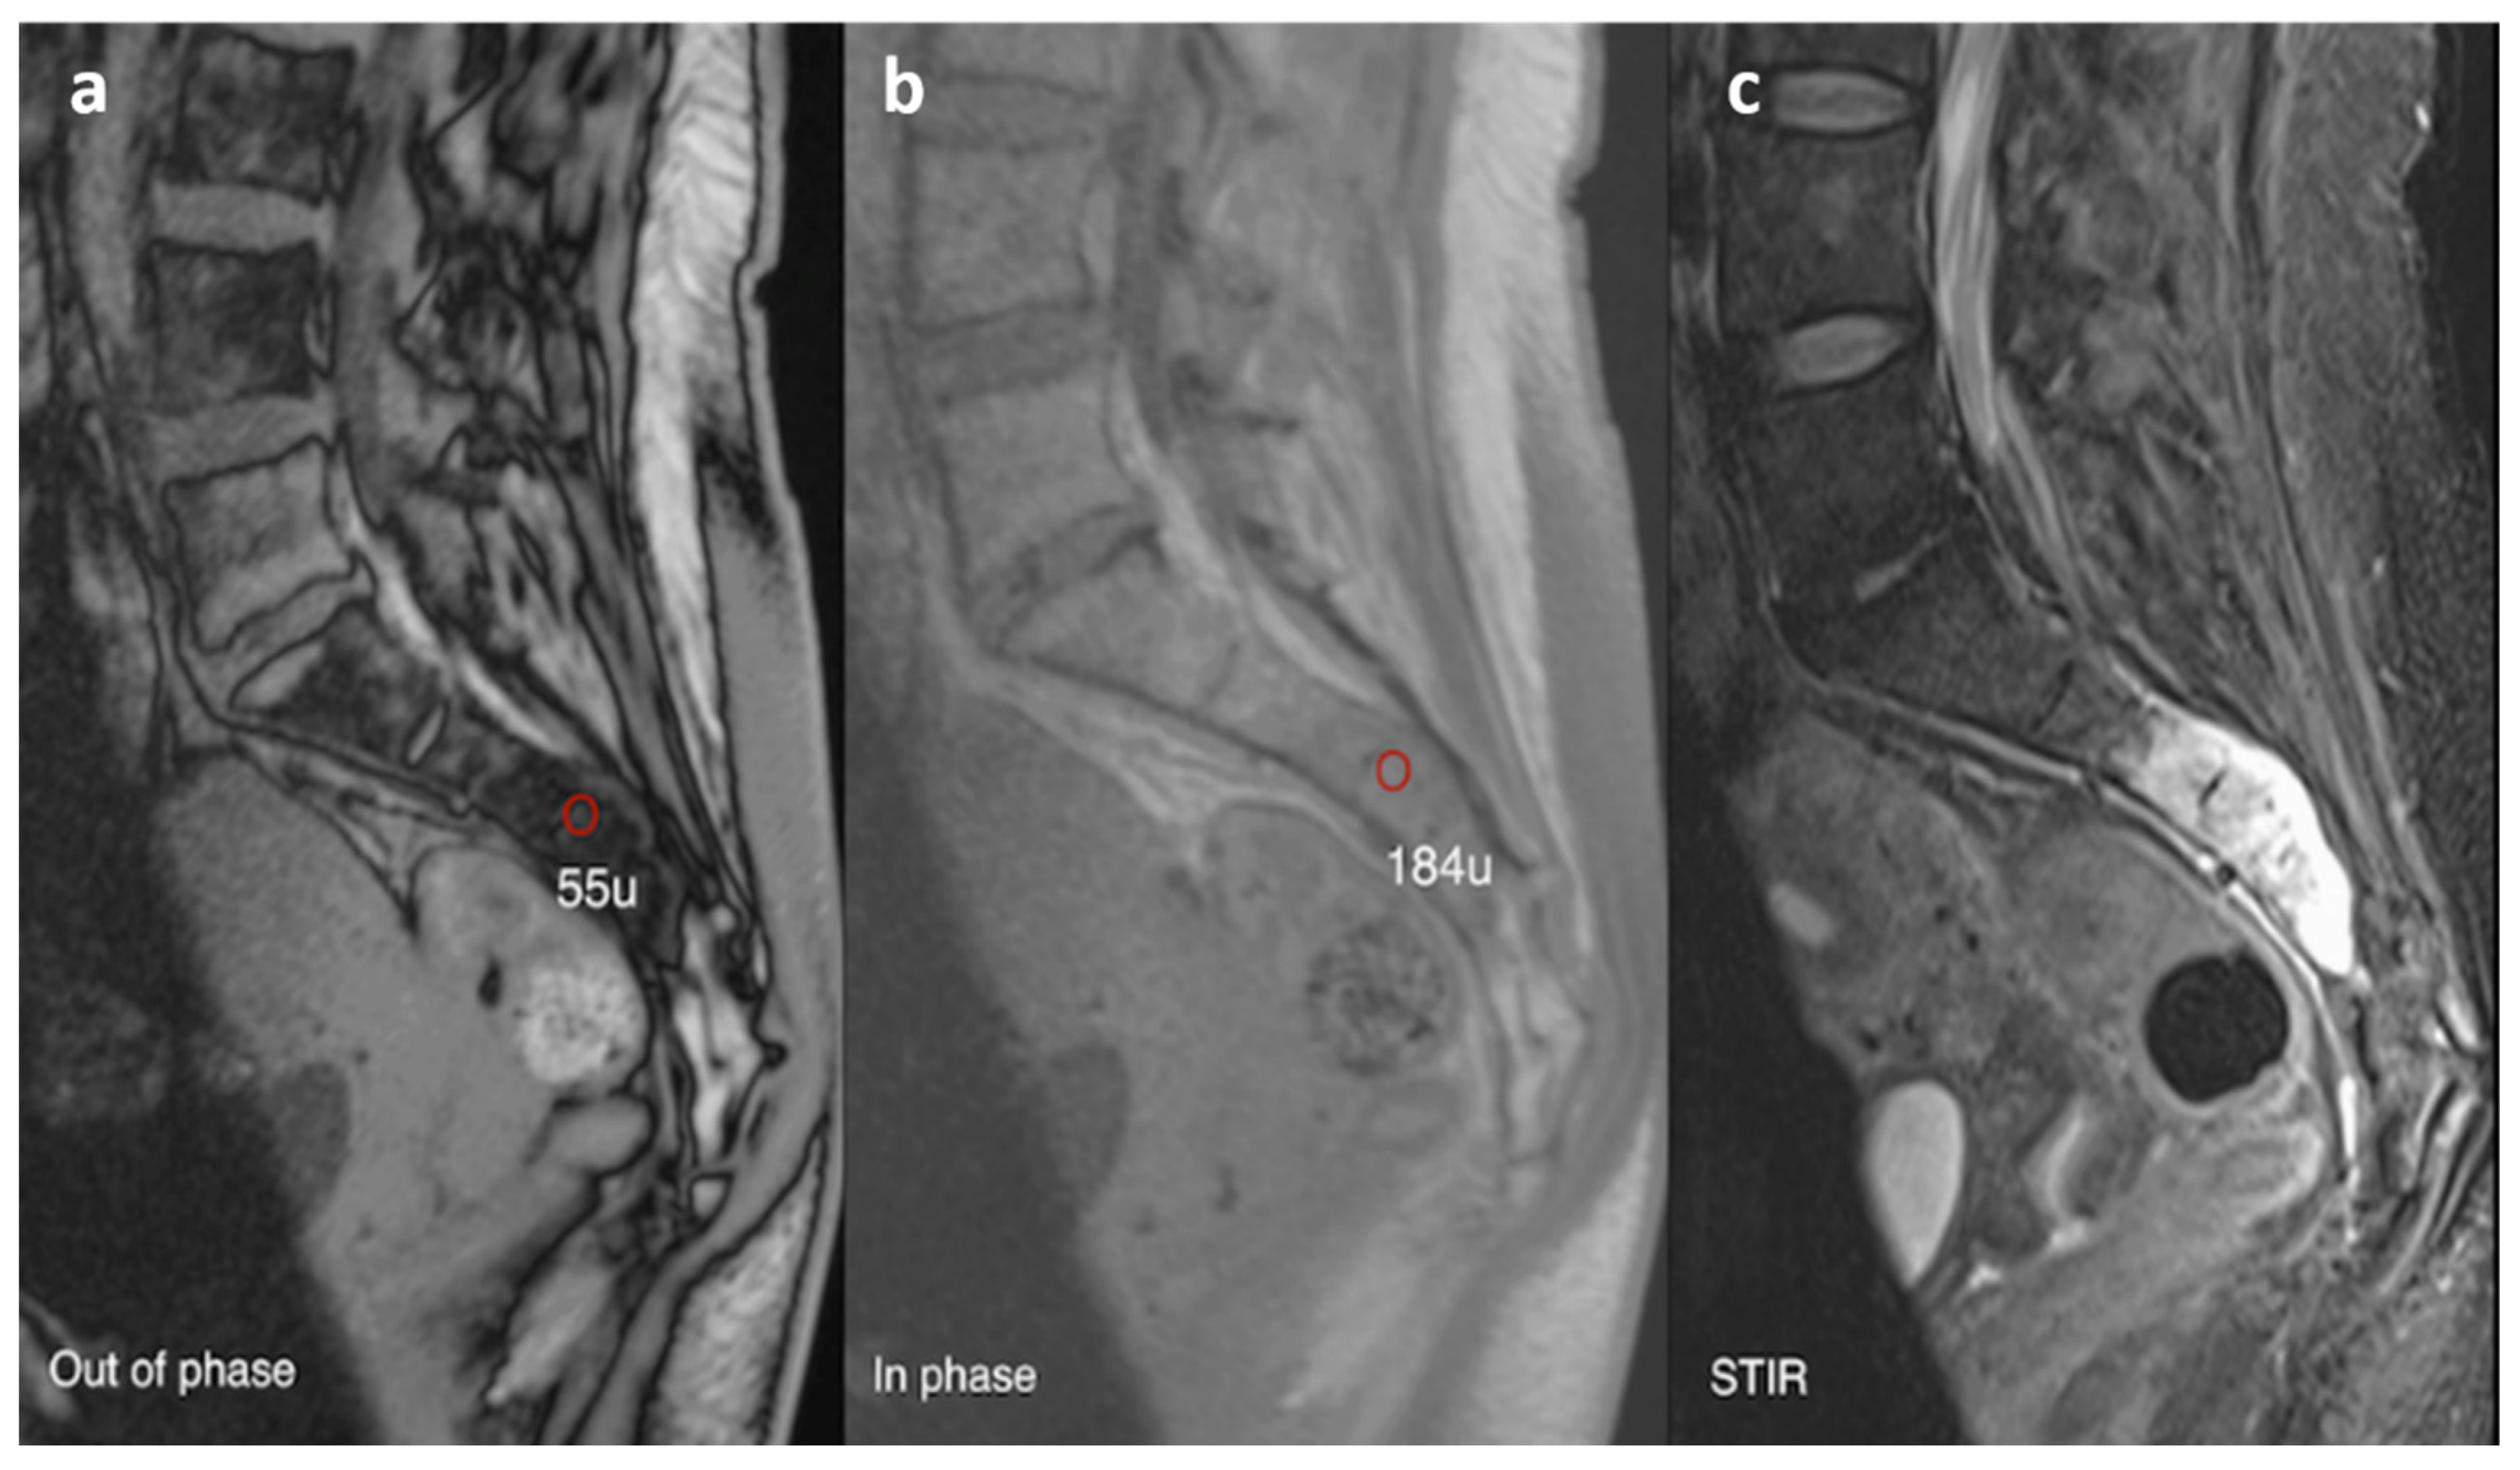

3.7. Haemangioma

| Haemangioma | Honey comb appearance. ‘Corduroy’ and ‘polka dot’ signs. | Usually T1 and T2 hyperintense due to fat content. Signal drop out >20% on out of phase chemical shift imaging. |